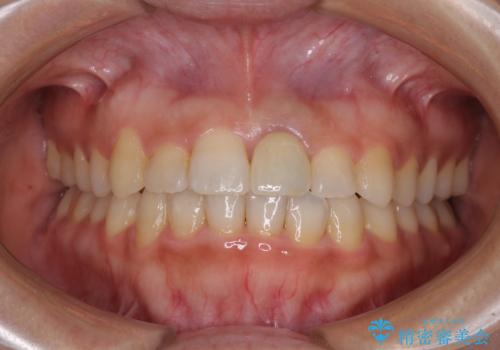

- 上下の八重歯を気にして来院された患者様です。

上下ともに八重歯の後ろの歯を1歯ずつ抜歯し、補助装置(リンガルアーチ)を用いて八重歯の位置を改善し、その後インビザラインにより矯正治療を行うこととしました。